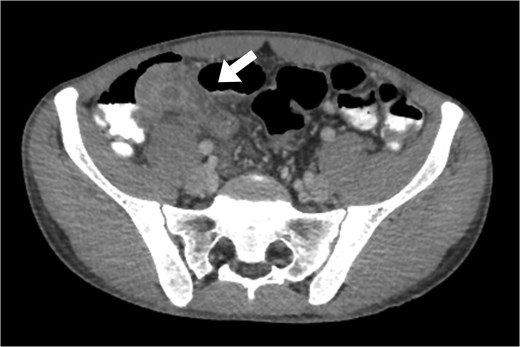

Abdominal computed tomography (CT) revealed a dilated appendix filled with fluid, measuring 2.7 × 8 cm on the short and long axes, respectively, with significant surrounding fat stranding, free fluid, and reactive inflammatory changes involving the terminal ileum and cecum, along with a few prominently enlarged regional lymph nodes (Fig. 1). Other investigations revealed a hemoglobin level of 12.6 g/dL, white blood cell count of 11.3 × 109/L with an absolute neutrophil count of 10.3 × 109/L, and erythrocyte sedimentation rate of 64 mm/h.

Axial view of abdominal and pelvic CT scan with oral and IV contrast shows enlarged appendix, measured 2.7 in diameter. Surrounded by fat-stranding, free fluid, with enlarged reactive lymph nodes (arrow).